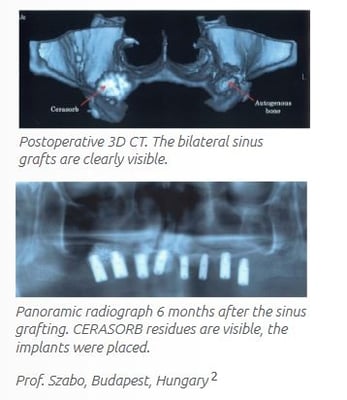

• In a bilateral sinus lift study, results suggest CERASORB is an equivalent graft material to autogenous bone.5

5. Szabo G, Huys, et al. International Journal of Oral and Maxillofac Implants 2005; 20:371-381.